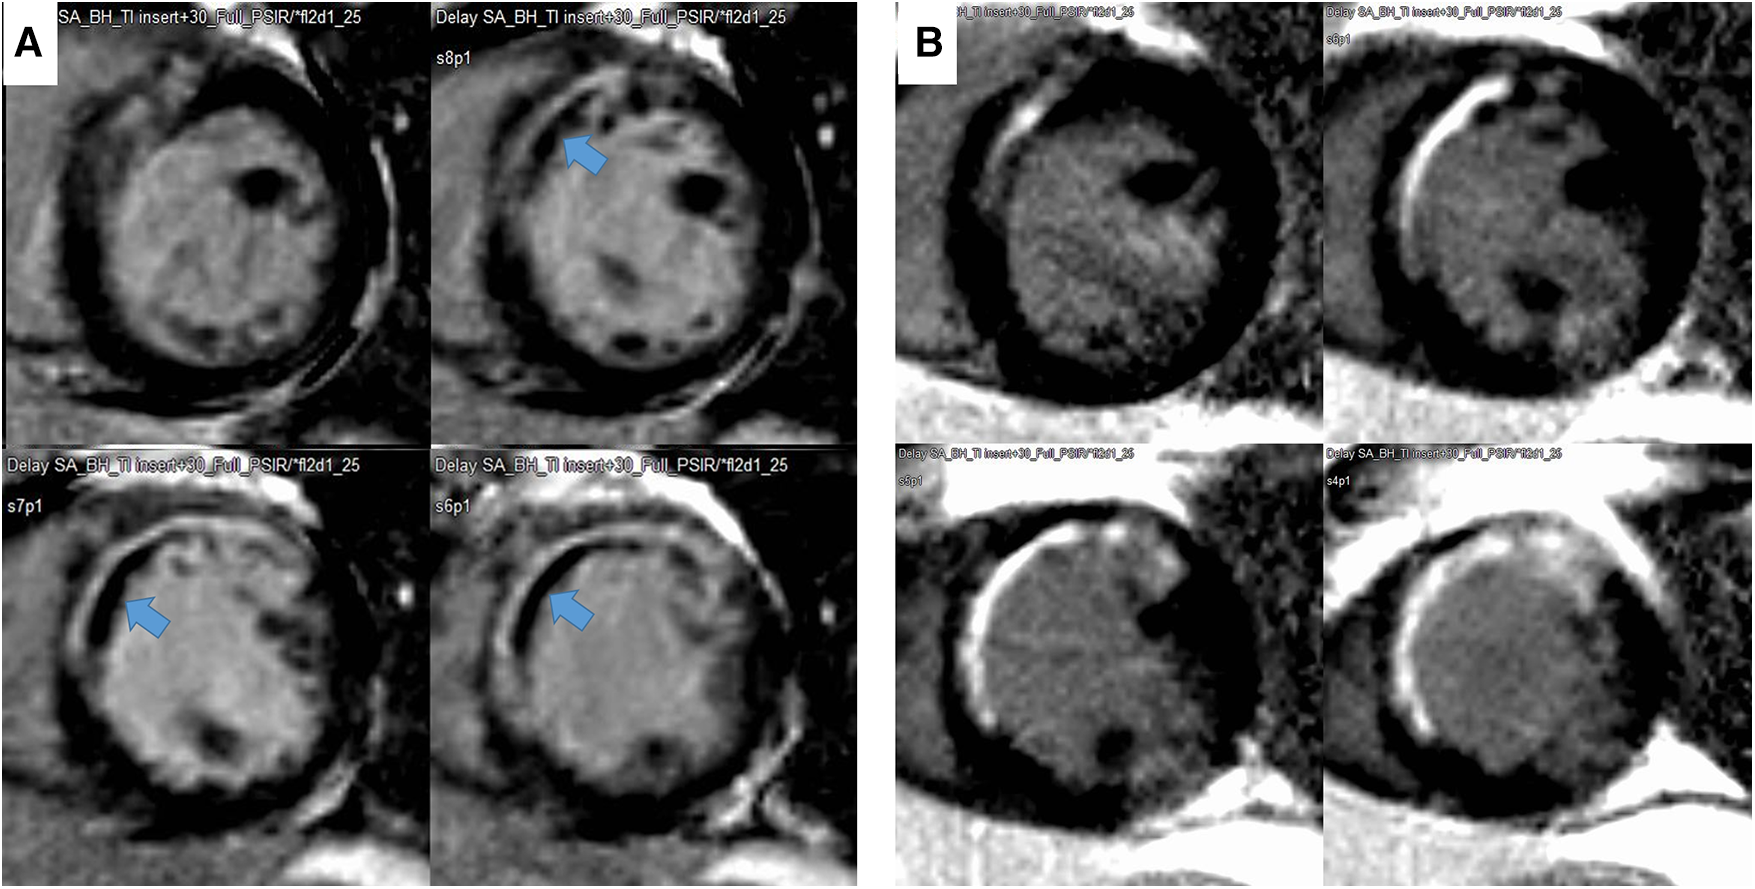

The endocardial and epicardial borders were contoured using a semiautomated method (QMassMR version 8.1, Leiden, Netherlands). To determine the end-diastolic LV mass, the difference between the epicardial and endocardial areas for all slices was multiplied by the slice thickness and section gap and then multiplied by the specific gravity of the myocardium (1.05 g/ml). Papillary muscle mass was included in the LV cavity and excluded from the LV mass measurements. The endocardial areas for all short-axis slices were measured at the end diastole and end systole. From the LGE images, the LV was divided into 16 segments. MVO was defined as a hypoenhanced region in the infarct-related myocardium (Figure 2). The MVO lesion was included in the LGE area. The extent of myocardial scarring, defined as the absolute amount of LGE (g) and percentage of LGE, was measured using dedicated quantitative analysis software (QMassMR version 8.1, Medis, Leiden, Netherlands). The MVO area and its percentage were also automatically measured within the LGE area. In each short-axis slice image, the boundaries of contrast-enhanced areas were automatically traced (using a full-width at half-maximum method that defines the enhanced area by using 50% of the maximum signal found within the enhanced area) (8). The maximum signal was determined using computer-assisted window thresholding of the enhanced area. Obvious artifacts, such as those caused by motion, were excluded by highlighting them using a tool from the software package. Other small isolated regions of enhancement that were not of ischemic origin were also excluded from the analysis. The total infarct size was calculated by the summation of all slice volumes of enhancement, and a 16-segment model was used.

Figure 2

Representative case of a decrease in infarct size and disappearance of microvascular obstruction (MVO) during follow-up. The MVO (black within white, indicated with an arrow) within the late gadolinium enhancement area in the initial image (A) and change to LGE during the 9-month follow-up (B).

Changes in infarct size and LV systolic and diastolic function during follow-up

The LVEDVs (r = 0.791, p < 0.001), LVESVs (r = 0.858, p < 0.001), and LVEFs (r = 0.744, p < 0.001) measured in short-axis and long-axis views were significantly correlated with each other. For the analysis, the values from the long-axis view were used. LVEF and LV-GLS were significantly improved over 9 months, from 47.4 ± 9.6% to 51.5 ± 9.5% (p < 0.001) and from −13.6 ± 4.2% to −15.0 ± 4.3% (p < 0.001), respectively, along with significant decreases in LV mass (124.2–105.9, p < 0.001), LVEDV (159 ml–153 ml, p = 0.023), and LV-Ed (0.133 1/ml–0.127 1/ml, p = 0.049) and an increase in DT of early mitral inflow (188.6 ms–226.3 ms, p < 0.001). Regarding infarct size, %LGE amount and absolute LGE mass (g) significantly decreased during the 9-month follow-up, from 20.9 (8.5–26.8)% to 11.1 (7.0–20.0)% and from 18.2 (4.5–30.6) g to 10.3 (5.6–17.7) g, respectively (both p < 0.001) (Table 1 and Supplementary Figure S1). All MVO lesions disappeared and were changed to LGE on follow-up CMR (Figure 2). Additionally, both the average ECV of the initial LGE-involved segments (42.1 ± 6.4%–36.4 ± 6.3%, p < 0.001) and the average ECV of non-LGE-involved segments (32.5 ± 3.8–28.6 ± 2.2%, p < 0.001) significantly decreased during follow-up. Absolute LGE mass at 9 months was inversely correlated with LVEF (r = −0.618, p < 0.001) and correlated with LV-GLS (r = 0.596, p < 0.001). Regarding diastolic function, DT (r = −0.277, p = 0.027) and LA-GLS (r = −0.362, p = 0.002) were significantly correlated with LGE mass. But, e′, E/e′, LA volume index, and TRV were not significantly correlated with LGE mass. The average longitudinal strain (LS) of LGE-involved segments was significantly improved (from −16.6 ± 4.9% to −18.3 ± 5.1%, p = 0.001), while there was no significant change in non-LGE-involved segments. The LVEF, LV-GLS, and LS of LGE segments were significantly improved in both MVO presence and absence groups, but the degree of improvement was less prominent in the MVO group. The degree of DT prolongation during follow-up was less prominent in the MVO group (Figure 3). However, in both groups, both ECVs of initial LGE segments and non-LGE segments decreased during the 9-month follow-up (Table 2).